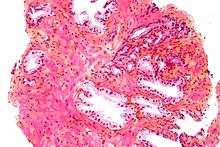

Histology

- Glandular cells

- Myoepithelial cells

- Subepithelial interstitial cells[17]

Prostate Microscopic glands of the prostate

Microscopic glands of the prostate Male Anatomy